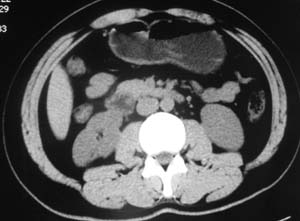

以下是引用子期在2010-3-19 20:47:00的发言:[br]血管畸形的ct增强应该有明显强化,本例并不相符合。本例双肾局部的略低密度影,累及肾盂,局部皮质明显变薄、内陷,增强扫描有轻度的强化,应考虑为炎性病变,患者为年轻男性,累及双肾的感染以结核较常见,可以没有明显的临床症状,尿中有时候也并不能查出什么;肾脓肿常有明显感染中毒症状,本例不符,另外一般的肾盂肾炎或肾小球肾炎通过小便就可确诊,其它还不能排除的是黄色肉芽肿性肾盂肾炎,然而单凭ct一般也很难鉴别。